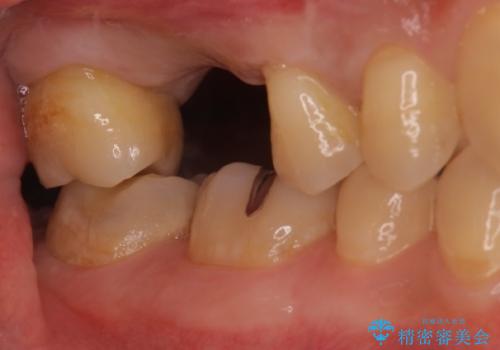

![[ 重度歯周病 ] 抜歯後のインプラント治療の症例 治療前](https://seimitsushinbi.jp/wp/wp-content/uploads/2023/09/175b509ec454b727ff977cee78485926-500x350.jpg?v=1695801041)